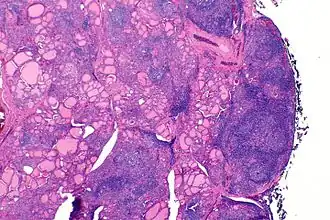

| Аутоиммунный тиреоидит (тиреоидит Хашимото) — гистологическая картина | |

Аутоиммунный тиреоидит (тиреоидит Хашимото, АИТ, хронический аутоиммунный тиреоидит, лимфоцитарный тиреоидит; лат. morbus Hasimoti, thyreoiditis Hasimoti, struma lymphocytaria, struma lymphomatosa, struma autoimmunea, struma Hasimoti) — хроническое воспалительное заболевание щитовидной железы аутоиммунного генеза, при котором в результате хронически прогрессирующей лимфоидной инфильтрации происходит постепенная деструкция паренхимы щитовидной железы с возможным исходом в первичный гипотиреоз. Впервые заболевание было описано японским хирургом Х. Хасимото в 1912 г. Он наблюдал несколько случаев увеличения ЩЖ, обусловленного лимфоидной инфильтрацией (лимфоматозный зоб), в связи с чем термином тиреоидит Хашимото обозначают гипертрофический вариант АИТ, хотя очень часто его распространяют на хронический АИТ в целом.

Заболевание развивается на фоне генетически детерминированного дефекта иммунного ответа, приводящего к Т-лимфоцитарной агрессии против собственных тиреоцитов, заканчивающейся их разрушением. Гистологически при этом определяются лимфоцитарная и плазмоцитарная инфильтрация, онкоцитарная трансформация тиреоцитов (образование клеток Гюртле-Ашкенази), разрушение фолликулов. АИТ имеет тенденцию проявляться в виде семейных форм. У пациентов с повышенной частотой обнаруживаются гаплотипы HLA-DR3, DR5, В8. В 50 % случаев у родственников пациентов с АИТ обнаруживаются циркулирующие антитела к ЩЖ. Кроме того, наблюдается сочетание АИТ у одного и того же пациента или в пределах одной семьи с другими аутоиммунными заболеваниями - пернициозной анемией, аутоиммунным первичным гипокортицизмом, хроническим аутоиммунным гепатитом, сахарным диабетом 1 типа, витилиго, ревматоидным артритом и др.